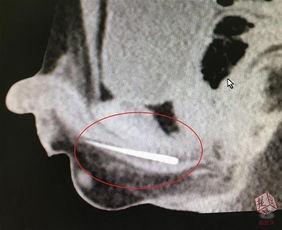

3. 疾病诊断视频:通过展示尿道疾病的症状和治疗方法,帮助患者了解自己的病情,为就医提供参考。

4. 手术演示视频:这类视频展示了尿道手术的过程,让医学专业人士学习手术技巧。